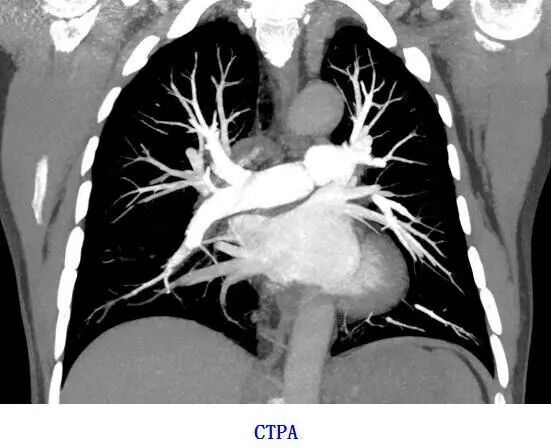

1、CT血管造影(CTA):可以评估血管及脏器功能,准确判断出血、栓塞、血管瘤、血管畸形、血管狭窄,肿瘤供血等情况,为治疗提供有效帮助。

联影ct怎么样【医讯】勐腊县人民医院引进国产联影高端64排128层螺旋CT正式投入使用_https://www.jmylbn.com_新闻资讯_第5张